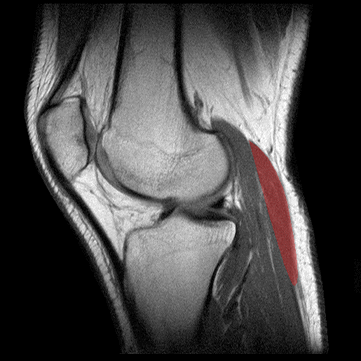

MUSCULO GEMELO EXTERNO

Definici�n: los m�sculos gemelos formados por las cabezas medial y lateral se extienden en la parte superficial del compartimento posterior de la pantorilla.

Origen: Las cabezas medial y lateral del m�sculo gemelo salen de los c�ndilos medial y lateral del f�mur, respectivamente. Las dos cabezas se unen en la parte superior de la pantorilla.

Inserci�n: El m�sculo forma un tend�n ancho y plano a nivel de la pantorrilla media. El tend�n soleo se insera en la parte anterior del tend�n del gemelo para formar el tend�n de Aquiles que, a su vez, se inserta en la parte posterior del calc�neo posterior